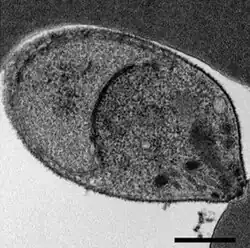

A Plasmodium knowlesi merozoite attaching to a red blood cell

As an apicomplexan, P. knowlesi has several distinctive structures at its apical end that are specialized for invading host cells. These include the large bulbous rhoptries, smaller micronemes, and dispersed dense granules, each of which secretes effectors to enter and modify the host cell.[6][7] Like other apicomplexans, P. knowlesi also has two organelles of endosymbiotic origin: a single large mitochondrion and the apicoplast, both of which are involved in the parasite's metabolism.[8]